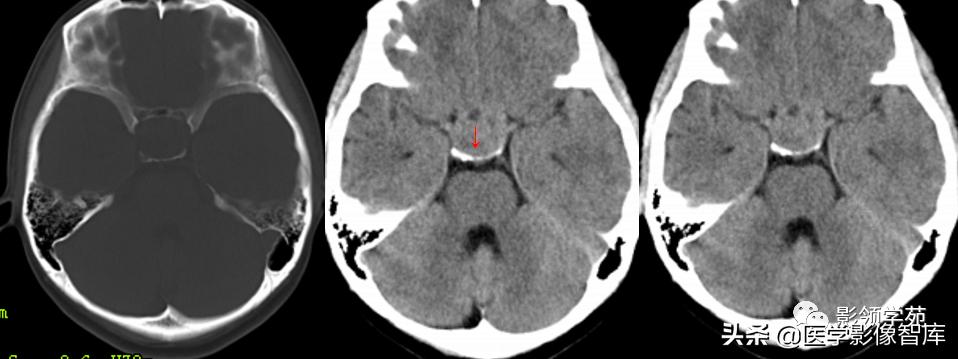

男,2岁,双视力障碍

鞍区见一类圆形囊性肿块,呈长T1长T2信号,囊壁厚薄不均。

囊壁呈环状强化,囊内未见明显强化。病灶占据蝶鞍、鞍上池及第三脑室前部,边缘清楚。

鞍区见一类圆形囊性肿块,囊壁呈蛋壳样钙化。肿块向下压入蝶鞍,向上达到第三脑室水平。

男 17岁,语言异常、视力减退、尿*禁失**、昏睡1月余。

鞍上池-第三脑室见一类圆形囊实性占位,边界清晰,内部以囊性长T1、长T2信号为主,信号均匀;另在囊下壁可见多发结节状实性病灶,呈乳头状向囊内凸起。

囊内实性病灶及囊壁明显强化,囊内容物无强化。视交叉受压向前移位,垂体可见,但垂体柄显示不清。中脑结构向后移位,中脑导水管通畅。

第三脑室明显变窄,双侧侧脑室、第四脑室外形正常。肿块邻近脑实质呈受压改变,关系清楚,无脑实质浸润及水肿信号。

(压迫视交叉、垂体柄、中脑;无梗阻性脑积水)